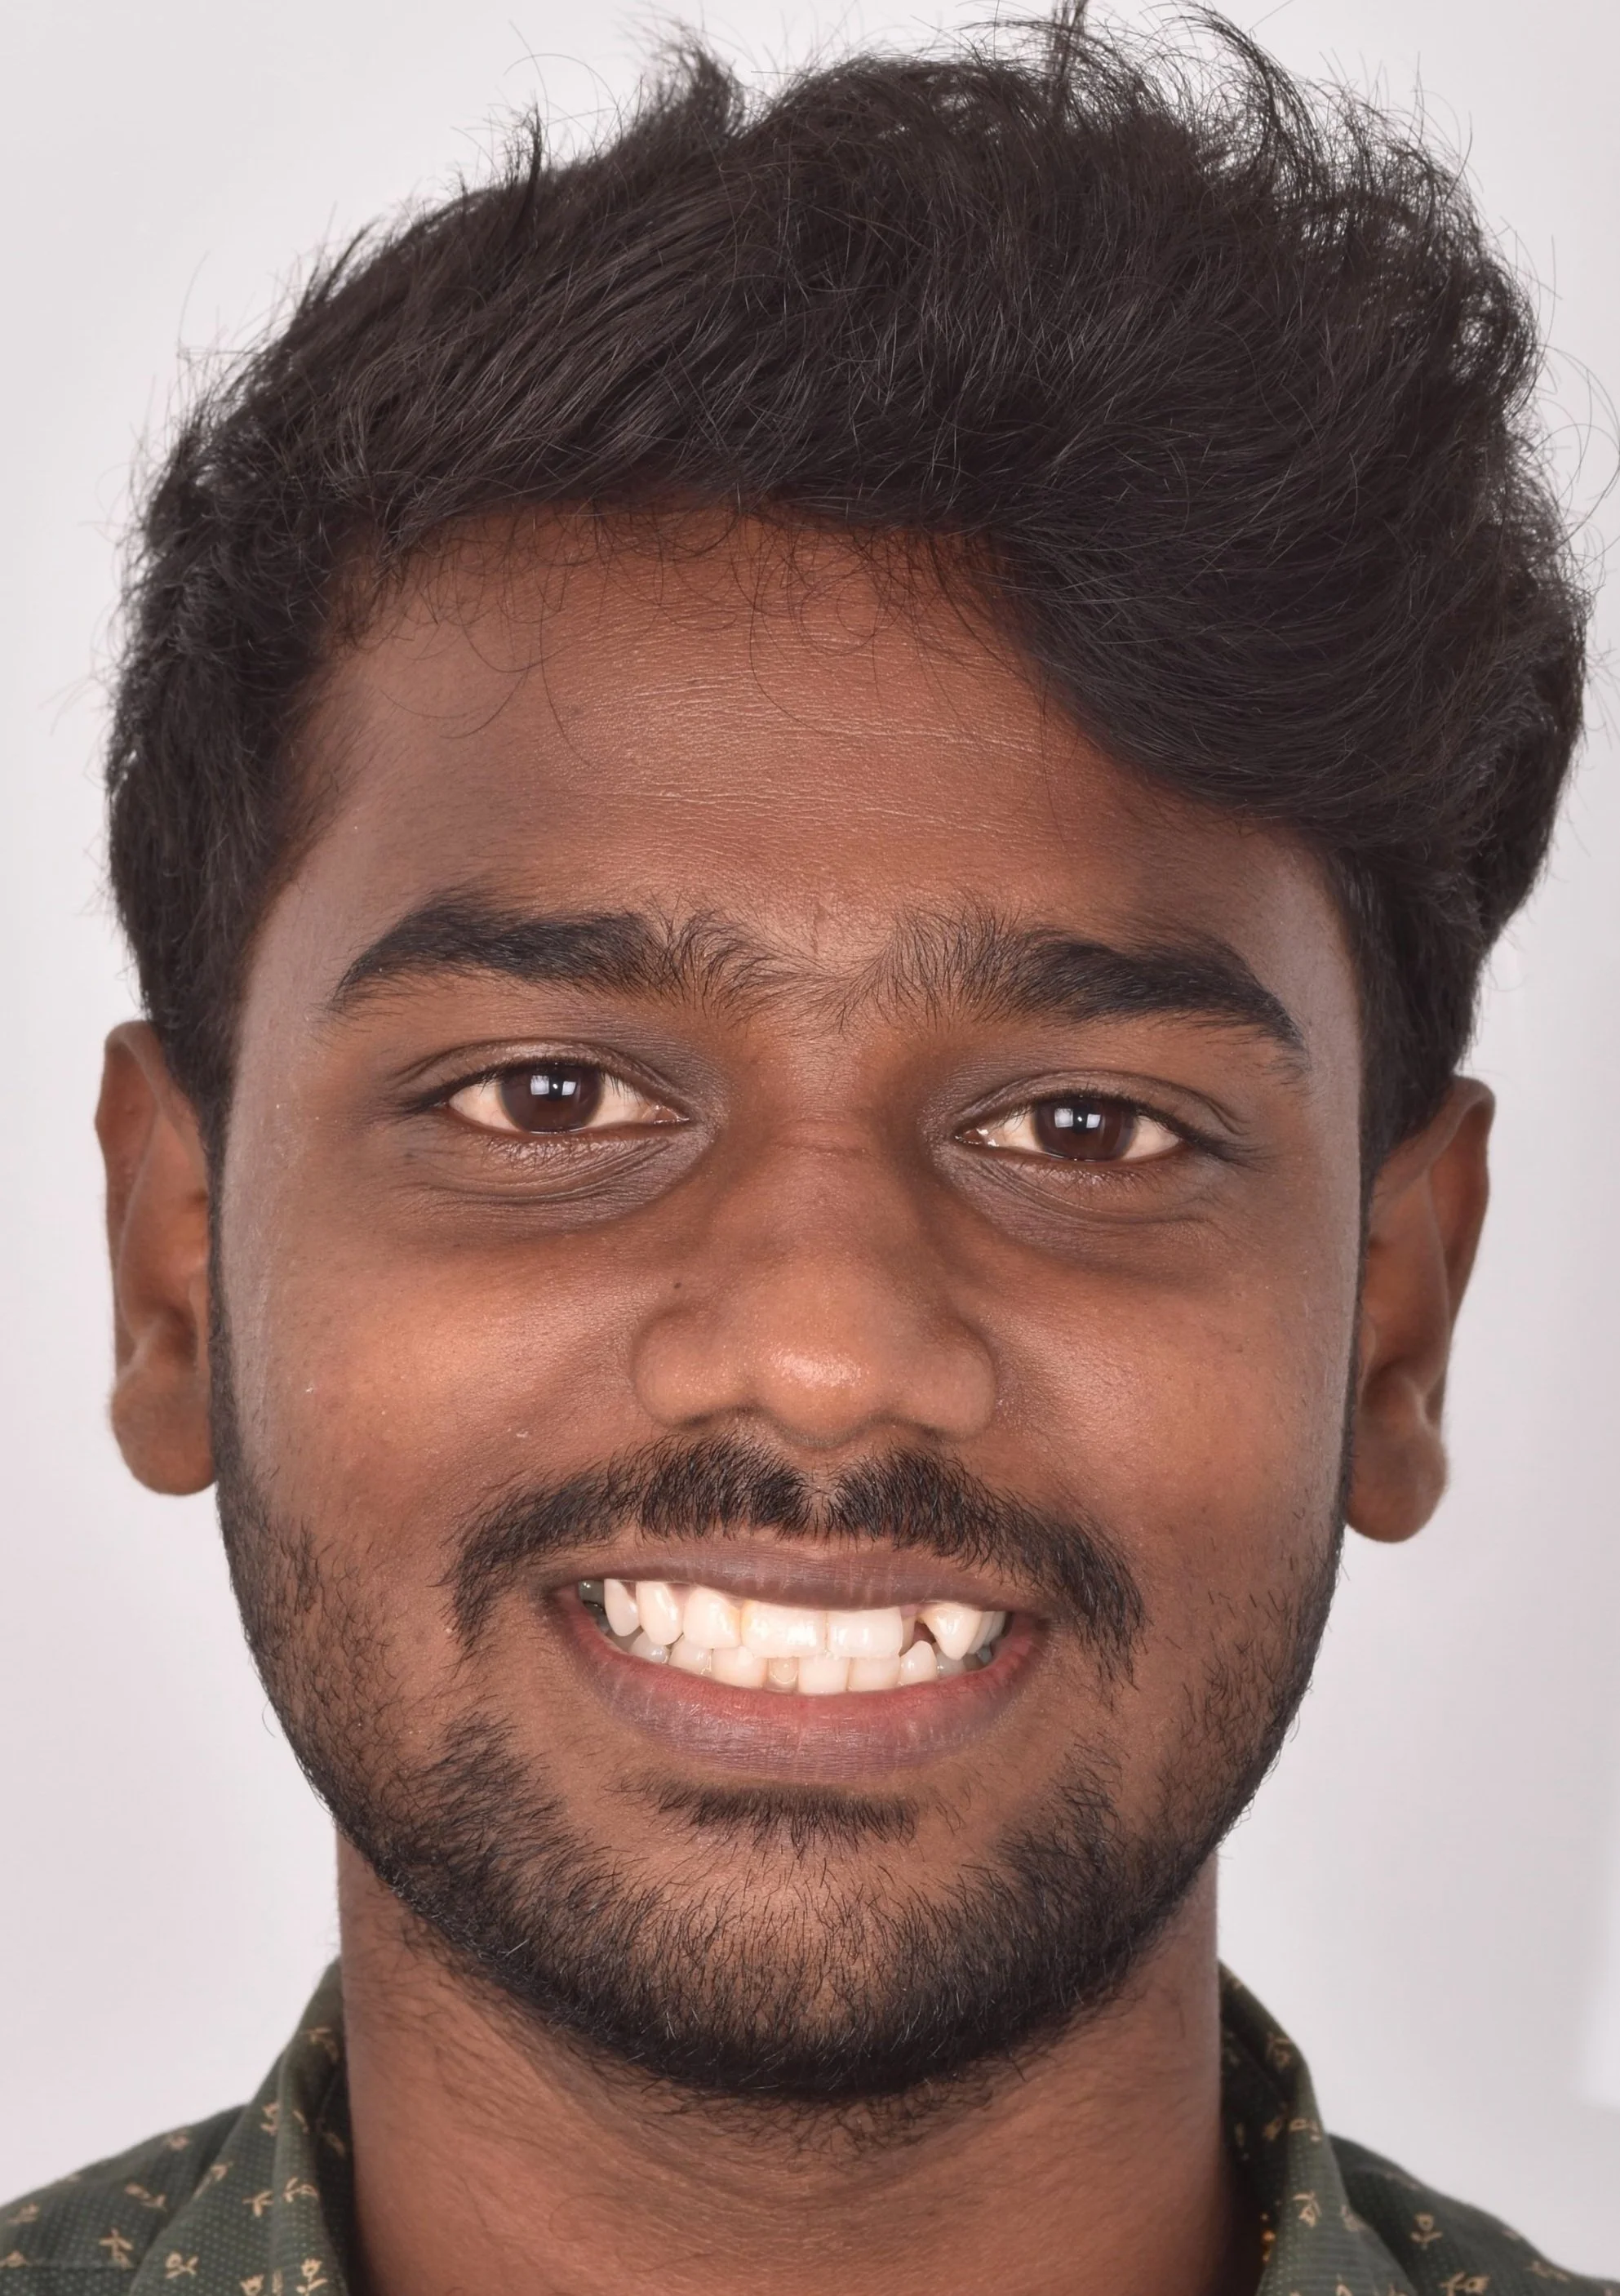

ARCH ALIGNMENT - DECROWDING THE MALPOSED TEETH

ARCH ALIGNMENT - DECROWDING THE MALPOSED TEETH

DECROWDING THE MALPOSED DENTITION

DECROWDING THE MALPOSED DENTITION